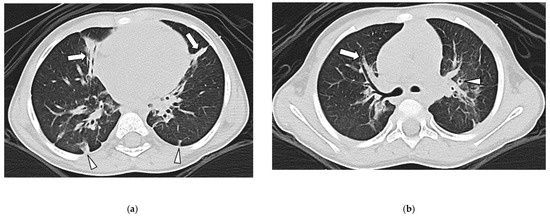

3.3. Lung Findings

3.4. Airway Findings

3.5. Pleural Findings

3.6. Interobserver Agreement

| GGO | 39/49 (76%) | 45/54 (83%) | 0.800 |

| TOL | 0/49 (0%) | 43/54 (80%) | <0.001 |

| Septal Thickening | 39/49 (76%) | 0/54 (0%) | <0.001 |

| Bronchial Wall Thickening | 0/49 (0%) | 33/54 (61%) | <0.001 |

| Bronchiectasis | 0/49 (0%) | 30/54 (56%) | <0.001 |

| Pleural Thickening | 44/49 (90%) | 2/54 (4%) | <0.001 |